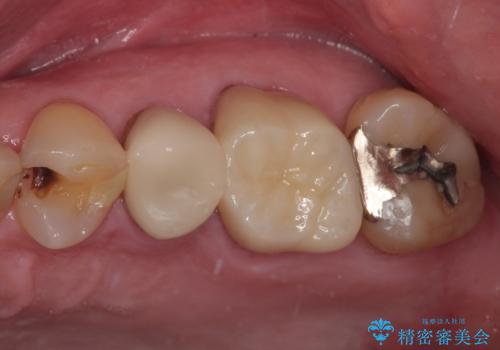

- 銀歯が取れたとのことで来院された患者様です。患者様の歯をあまり削りたくないというご希望に添い、セラミックインレーにて治療を行うこととなりました。

拡大鏡視野下で、保険のプラスチック、虫歯の除去を行い、セラミックインレーに適した形に整えました。